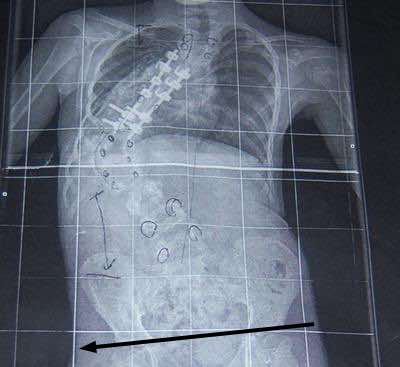

DEBILITATING SCOLIOSIS PAIN IN A 86 YEAR OLD FEMALE

RIGHT HIP NOW NEARLY FIVE (YES 5) INCHES HIGHER THAN LEFT.

HEIGHT DROPPED FROM TALLEST THREE AND ONE HALF INCHES ON RIGHT TO CURRENT FIVE FEET.